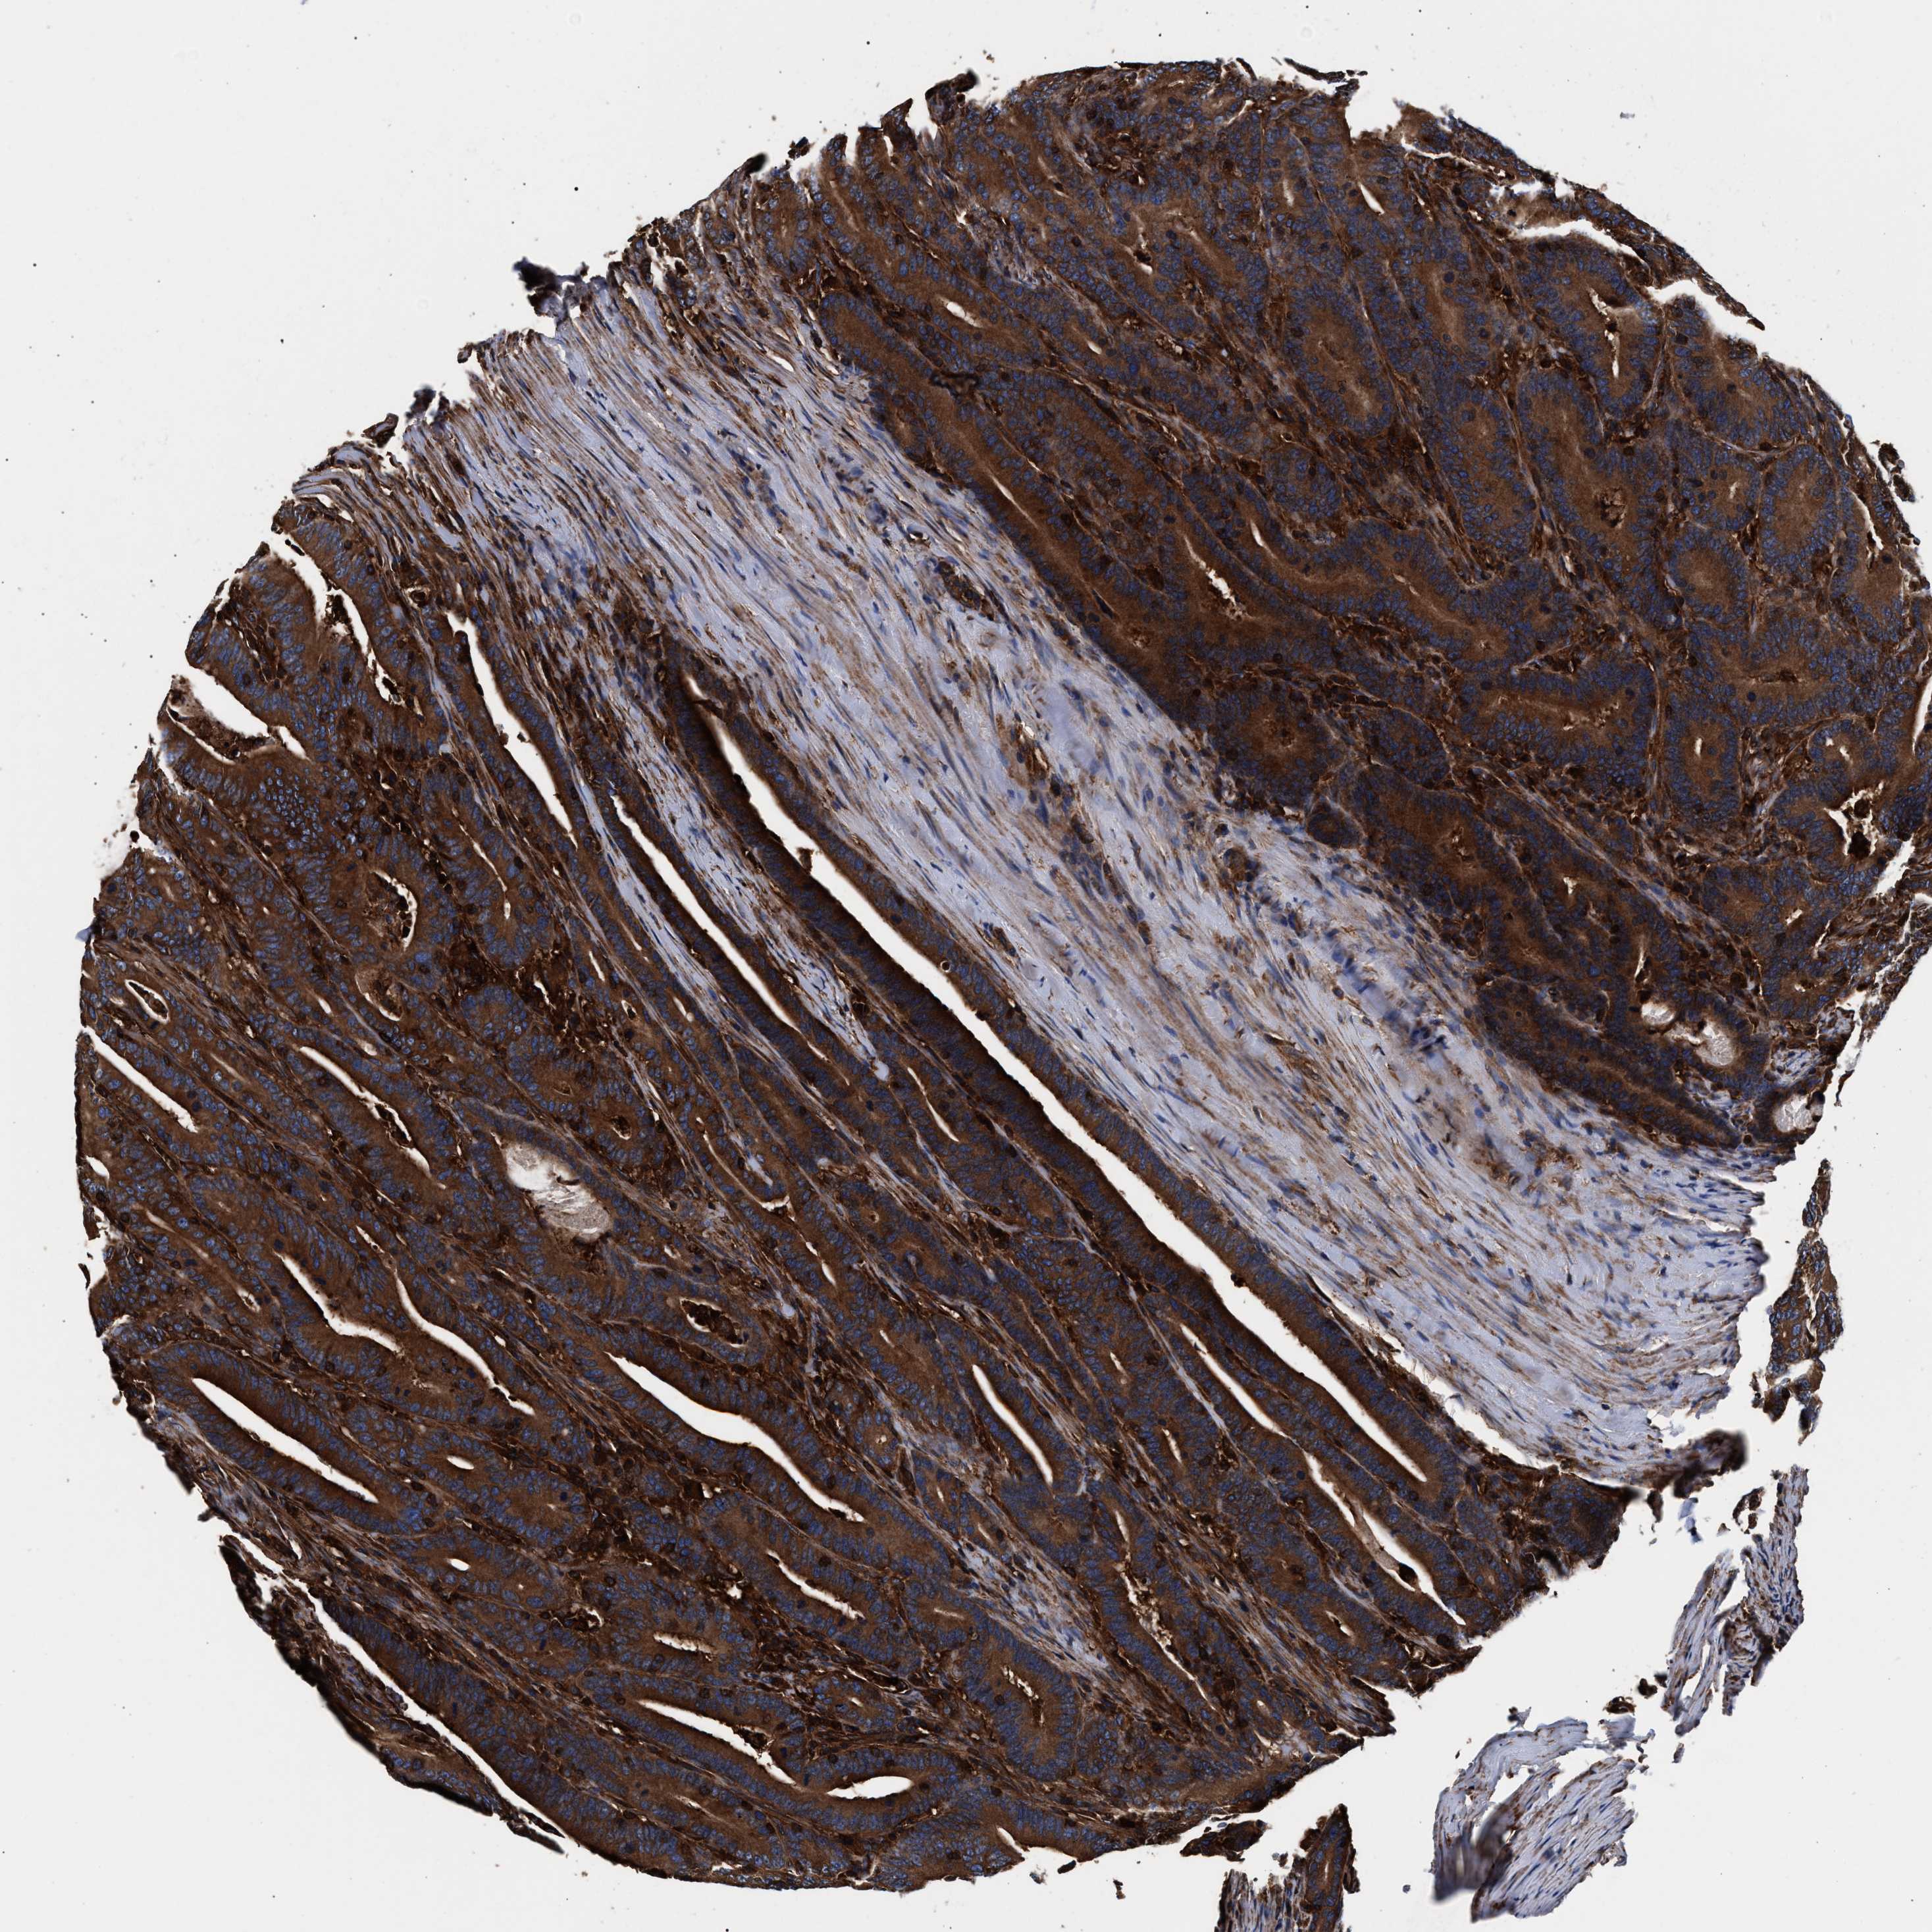

CANCER COLORECTAL CANCER Show tissue menu

Colorectal cancer

Human cancer

Colon adenocarcinoma